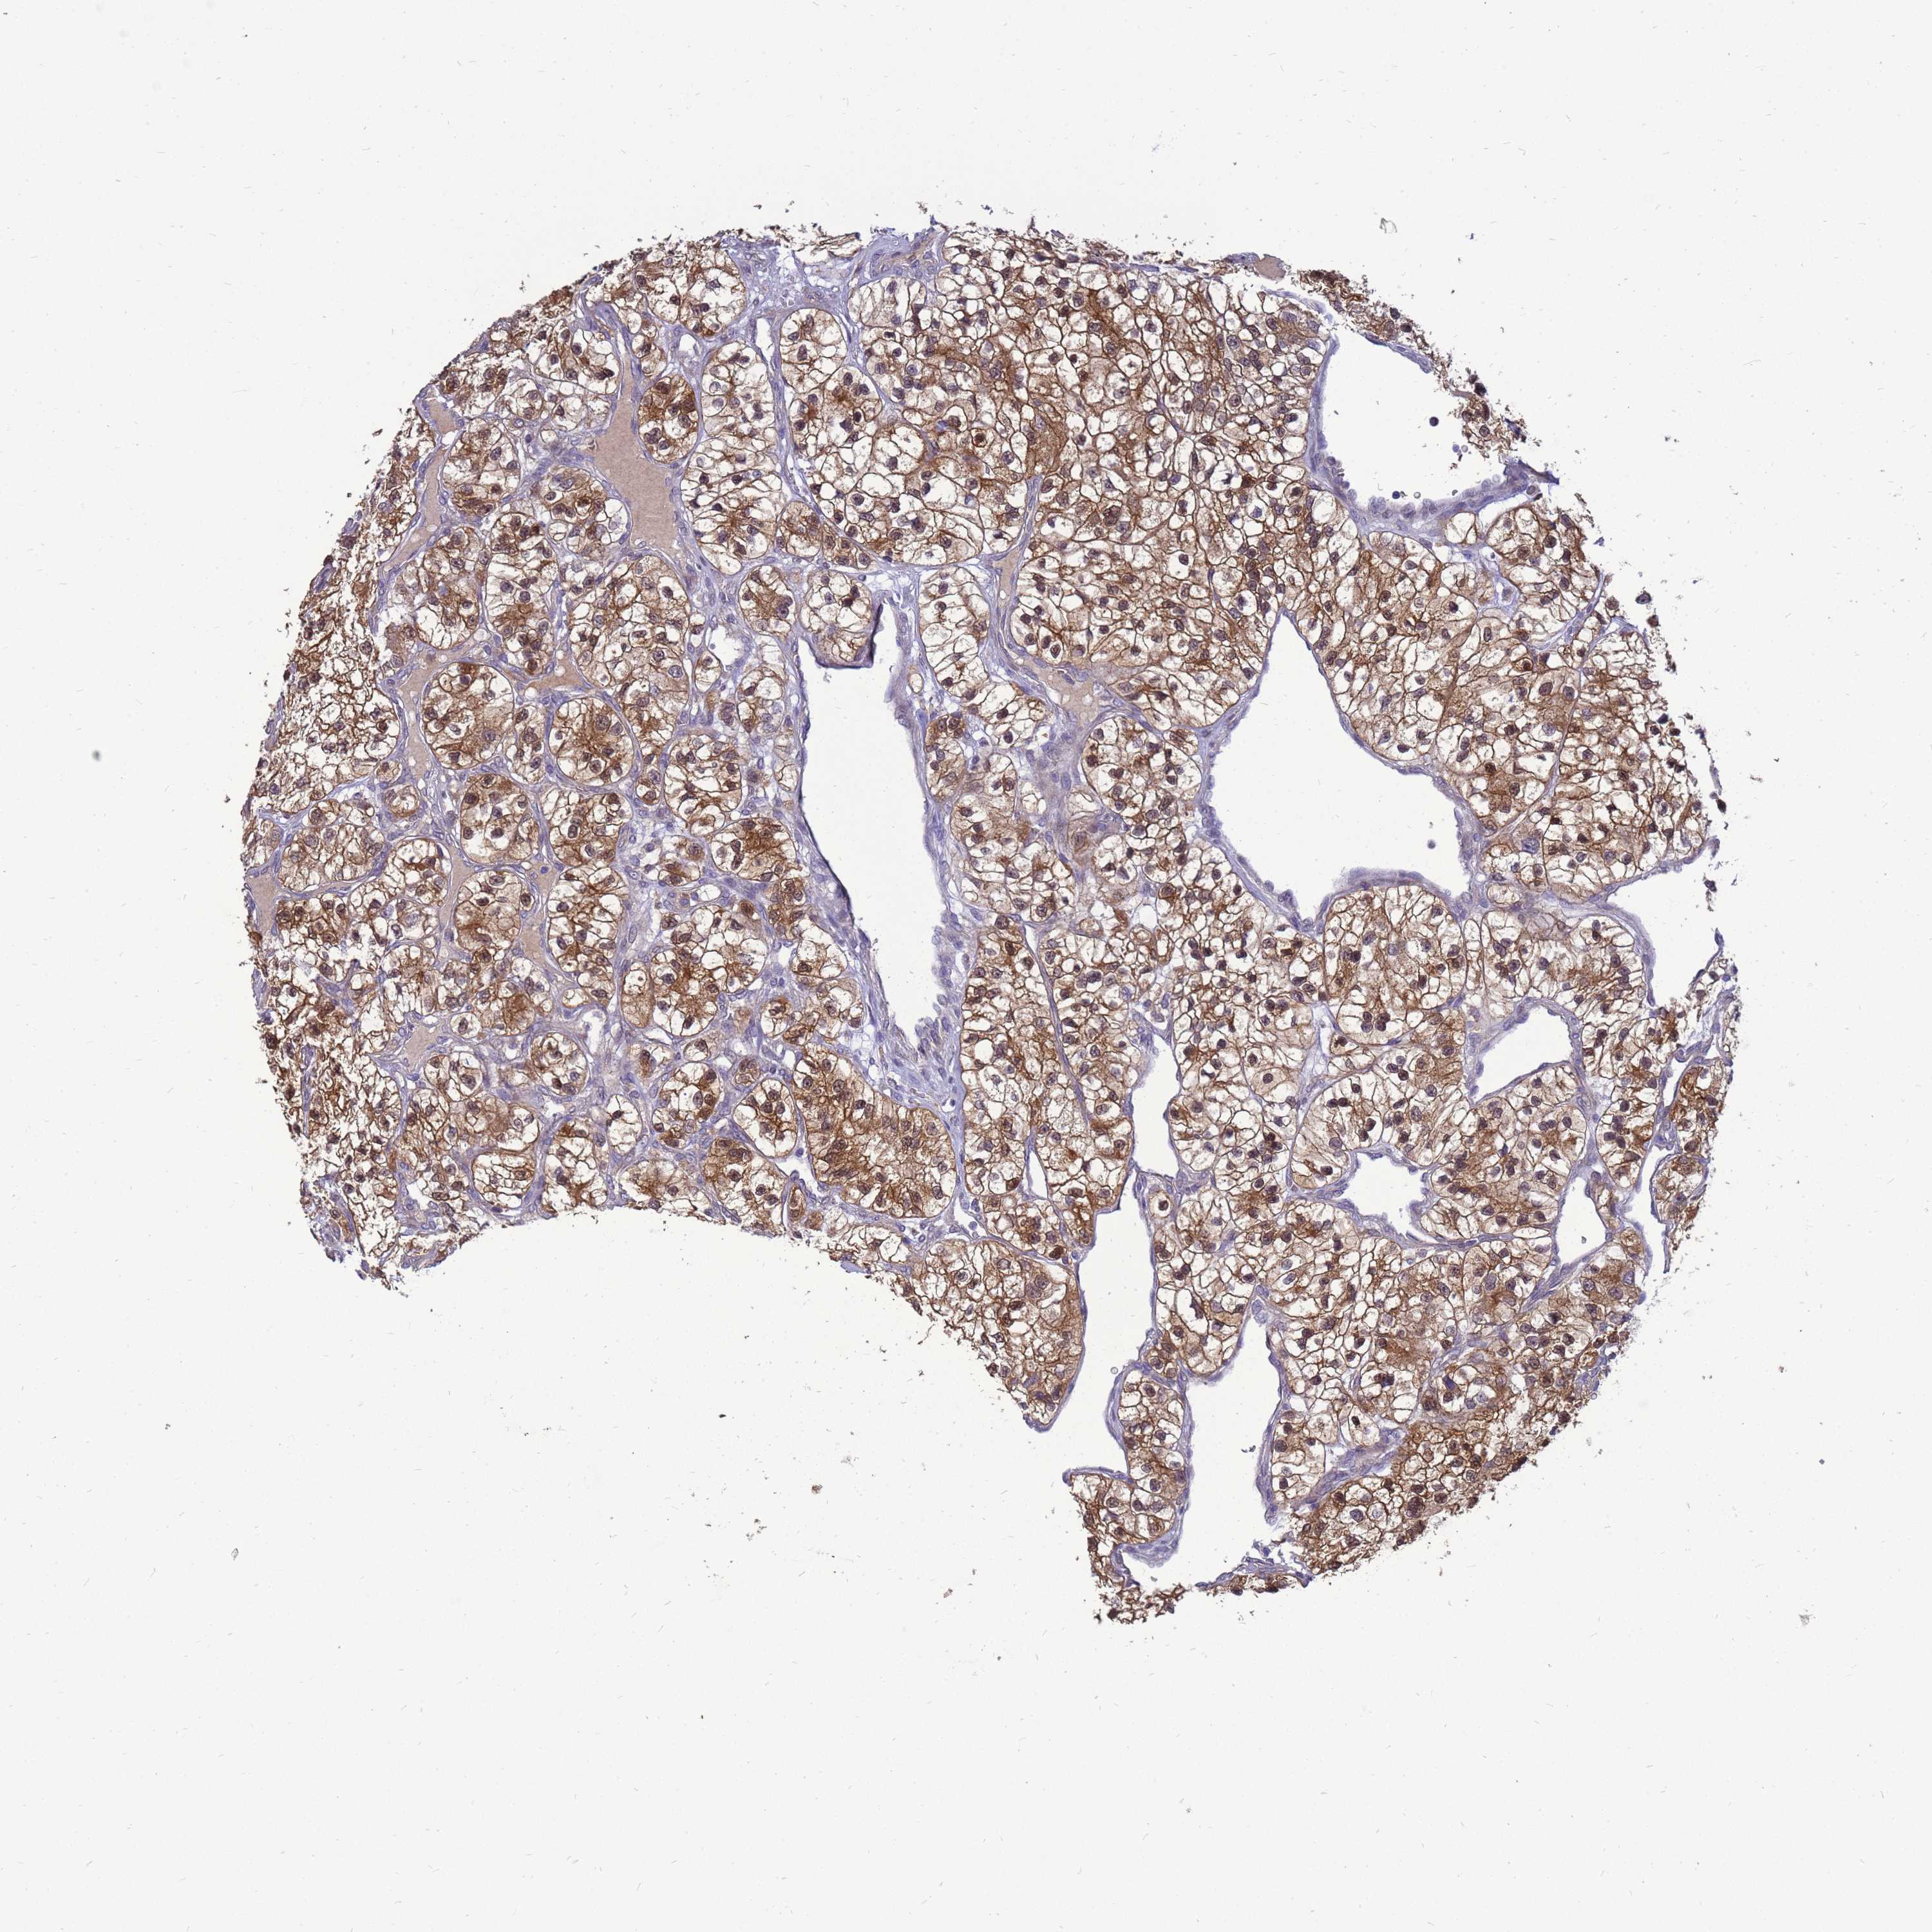

KIDNEY RENAL CLEAR CELL CARCINOMA (VALIDATION) - Interactive survival scatter ploti

The Survival Scatter plot shows the clinical status (i.e. dead or alive) for all individuals in the patient cohort, based on the same data that underlies the corresponding Kaplan-Meier plots. Patients that are alive at last time for follow-up are shown in blue and patients who have died during the study are shown in red.

The x-axis shows the expression levels (FPKM) of the investigated gene in the tumor tissue at the time of diagnosis. The y-axis shows the follow-up time after diagnosis (years). Both axes are complimented with kernel density curves demonstrating the data density over the axes. The top density plot shows the expression levels (FPKM) distribution among dead (red) and alive patients (blue). The right density plot shows the data density of the survived years of dead patients with high and low expression levels respectively, stratified using the cutoff indicated by the vertical dashed line through the Survival Scatter plot. This cutoff is automatically defined based on the FPKM cutoff that minimizes the p-score. The cutoff can be changed by dragging the vertical line or by entering a cutoff value in the square labeled "Current cut-off".

Under the Survival Scatter plot the p-score landscape (black curve; left axis) is shown together with dead median separation (red curve; right axis). Dead median separation is the difference in median mRNA expression between patients who have died with high and low expression, respectively. It is calculated as follows: median FPKM expression of dead patients with high expression - median FPKM expression of dead patients with low expression. This is intended to aid the user in visually exploring custom cutoffs and the associated p-scores and dead median separation.

Individual patient data is displayed and can be filtered by clicking on one or more of the category buttons on the top of the page. Categories describing expression level and patient information include: high, low, alive, dead, female, male and tumor stages. The scale of the x-axis can be toggled between linear and log-scale by clicking on the "x log" button. Mouse-over function shows TCGA ID, patient information and mRNA expression (FPKM) for each patient.

& Survival analysisi

Kaplan-Meier plots summarize results from analysis of correlation between mRNA expression level and patient survival. Patients were divided based on level of expression into one of the two groups "low" (under cut off) or "high" (over cut off). X-axis shows time for survival (years) and y-axis shows the probability of survival, where 1.0 corresponds to 100 percent.

EIF4EBP3 is not prognostic in Kidney Renal Clear Cell Carcinoma (validation)

Best expression cut offi

Based on the FPKM value of each gene, patients were classified into two groups and association between prognosis (survival) and gene expression (FPKM) was examined. The best expression cut-off refers the FPKM value that yields maximal difference with regard to survival between the two groups at the lowest log-rank P-value. Best expression cut-off was selected based on survival analysis .

When clicking on this number, the vertical dashed line indicating cut-off, the interactive survival plot, and the Kaplan-Meier curve will be adjusted to show results based on the best expression cut-off.

: 53.4

TCGA RNA samplesi

RNA-seq data is reported as average FPKM (number Fragments Per Kilobase of exon per Million reads), generated by the The Cancer Genome Atlas (TCGA) .

Normal distribution across the dataset is visualized with box plots, shown as median and 25th and 75th percentiles. Points are displayed as outliers if they are above or below 1.5 times the interquartile range. FPKM values of the individual samples are presented next to the box plot.

Average pTPM 62.1

Number of samples 100